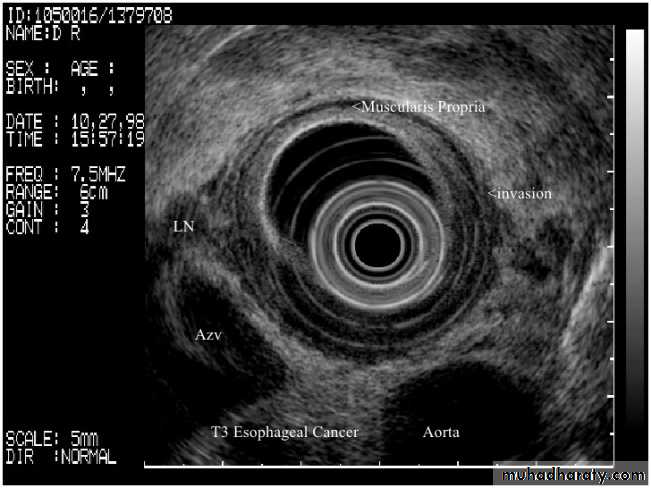

• Transrectal US (TRUS): guidance of prostate biopsy; staging of rectal cancer

• Endoscopic US (EUS): assessment of tumors of the upper gastrointestinal tract and pancreas